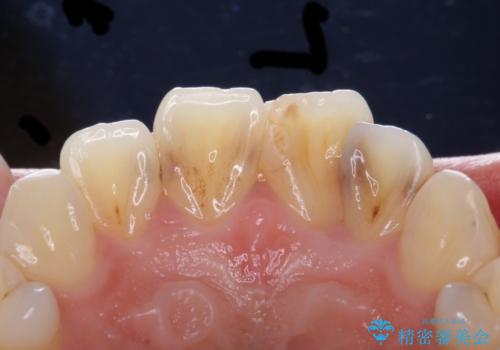

- 前歯をきれいにしたいとのご希望により来院された患者様です。

ご希望により、上の前歯4本のセラミッククラウンによる補綴治療を行いました。

- ¥572,000 (根管治療×1本、土台×1本、仮歯×4本、クラウン×4本) ※税込費用は治療当時の料金となります